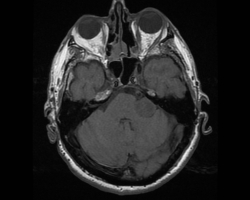

Un homme de 55 ans, n’ayant aucun antécédent personnel est envoyé pour réaliser une IRM par son ORL pour exploration d’acouphènes associés à une hypoacousie droite ainsi que des vertiges et une paralysie faciale périphérique droite d’apparition récente.